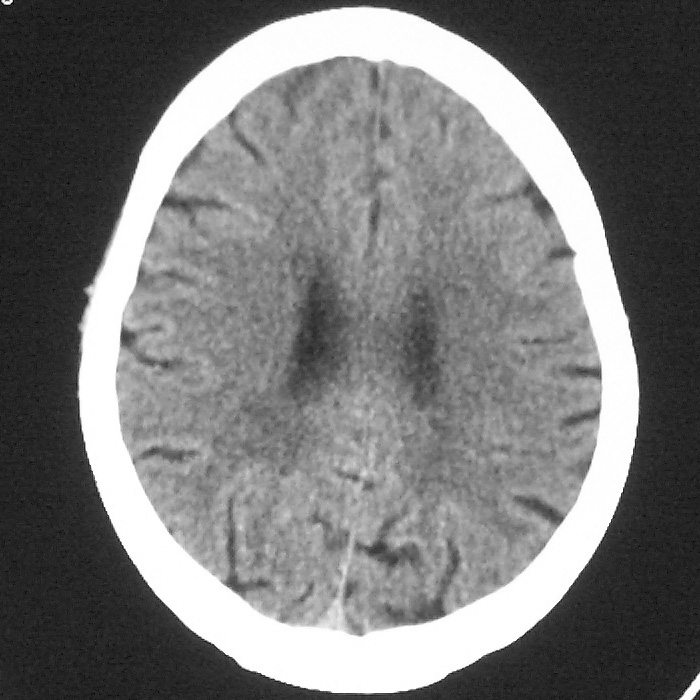

f,70y,口角歪斜、流涎、吐词不清三天

左侧大脑基底节区点状低密度影,边缘清楚,左侧腔梗或软化灶,没什么问题啊?

症状这么明显的话一般不会是单纯面神经麻痹引起的,最好做个mri,如果确实没有问题的话才能考虑面神经麻痹,毕竟这两种病的治疗和预后不一样,这个病人还有脑白质疏松。

左侧半卵圆中心腔梗应当比较明确,右侧基底节好象不明显,不好说,做个mri明确吧

双侧多发腔梗

右侧基底,左侧半卵圆中心腔梗

1、右侧基底,左侧半卵圆中心腔梗。2脑萎缩。

左侧腔隙性梗塞灶,脑萎缩。

左侧基底节区示点状低密度灶,边界清楚,密度均匀,余所示无著变。

意见:腔隙性脑梗塞(左基底节区)

各位老师,报告这么写可以吗?右侧我没有看出来。

左侧半卵圆中心,右侧基底节腔梗。再加个脑萎缩吧

双侧多发腔梗 脑萎缩